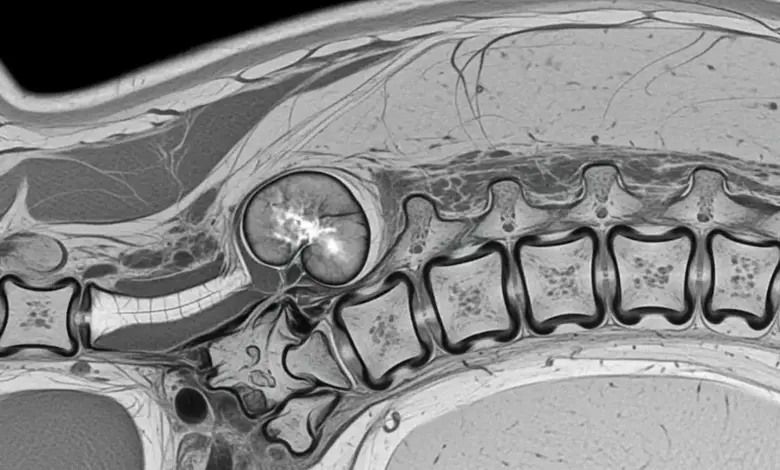

- Ressonância magnética: melhor exame para ver medula, canal vertebral, raízes nervosas e partes moles.

- Tomografia: ajuda a entender a destruição óssea e planejar a cirurgia.